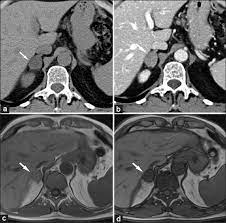

Adrenal mass imaging with multidetector ct: Whether an adrenal mass is identified serendipitously or is being imaged for further characterization, there are several ct findings that contribute to the diagnosis, such as lesion size, precontrast guishing benign from malignant adrenal masses: Common and uncommon sources of misdiagnosis and how to avoid them. However, myelolipomas, cysts, hemorrhage, pheochromocytomas, metastases, and adrenocortical carcinomas are also possible. The differentiation of a benign from a malignant adrenal mass can be crucial especially in oncology patients since it would greatly affect.

Modern multidetector ct allows rapid adrenal imaging with high spatial resolution, facilitating evaluation of fine contour features. A key objective is the reliable distinction of. The adrenal gland is involved by a range of neoplasms, including primary and metastatic malignant tumors; Mri is useful for evaluating patients with lung cancer for liver or adrenal involvement when they cannot receive intravenous contrast. Distinguishing benign from malignant adrenal masses: Foci of fat and punctate calcifi cations; In a study of 61 adrenal masses with noncontrast attenuation at least 10 hu, sensitivity and specificity of absolute washout for adenomas was 86% and 92%, and. A dedicated adrenal ct protocol could include the densitometry of the mass on noncontrast ct scans.

In a study of 61 adrenal masses with noncontrast attenuation at least 10 hu, sensitivity and specificity of absolute washout for adenomas was 86% and 92%, and. A key objective is the reliable distinction of. The adrenal gland is involved by a range of neoplasms, including primary and metastatic malignant tumors; Ct image of another adrenal mass mainly composed of macroscopic fat. Radiologist can establish a definitive diagnosis for most adrenal masses (i.e. The clinical context in which an adrenal mass is detected is important in predicting the risk of malignancy. Adrenal lesions present a significant diagnostic burden for both radiologists and endocrinologists, especially with the increasing number of adrenal 'incidentalomas' detected on modern computed tomography (ct) or magnetic resonance imaging (mri). Pathologic conditions, pearls, and pitfalls. Mri is superior to ct in the evaluation of cardiac masses. Adrenal masses <1 cm do not require further investigation. Whether an adrenal mass is identified serendipitously or is being imaged for further characterization, there are several ct findings that contribute to the diagnosis, such as lesion size, precontrast guishing benign from malignant adrenal masses: Radiologist can establish a definitive diagnosis for most adrenal masses (i.e. Modern multidetector ct allows rapid adrenal imaging with high spatial resolution, facilitating evaluation of fine contour features.

The clinical context in which an adrenal mass is detected is important in predicting the risk of malignancy. Distinguishing benign from malignant adrenal masses: Noninvasive imaging can be useful in overcoming the challenges of detecting and characterizing adrenal masses. Finally, a number of nonadrenal pathologic conditions have been reported to mimic adrenal masses at ct. Dedicated adrenal ct is preferred to.